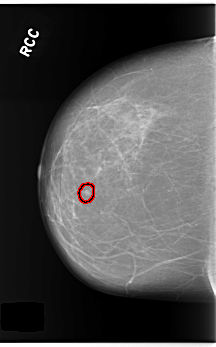

C_0253_1.RIGHT_CC

FILE: C_0253_1.RIGHT_CC.OVERLAY

TOTAL_ABNORMALITIES 1

ABNORMALITY 1

LESION_TYPE CALCIFICATION TYPE PUNCTATE DISTRIBUTION CLUSTERED

LESION_TYPE MASS SHAPE OVAL MARGINS CIRCUMSCRIBED

ASSESSMENT 4

SUBTLETY 5

PATHOLOGY BENIGN

TOTAL_OUTLINES 1

BOUNDARY